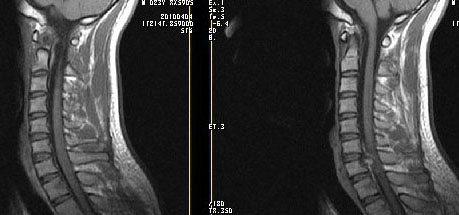

男24岁因一年来感头昏,查体四肢肌力及感觉无异常。颈椎dr未见异常,mri发现c7水平段椎管内左侧占位。患者于7年前有车祸伤病史(但是未检查,自述无异常)。请讨论是否是机化血肿或骨折片,能除外是肿瘤?

椎管内骨性肿块,与第7颈椎左下关节突关系密切,向椎管内生长,第7颈椎椎体左后缘受压变形,边缘可见硬化边,与肿块间间隙清晰。mri扫描肿块内可见骨髓信号,考虑骨软骨瘤可能性大。